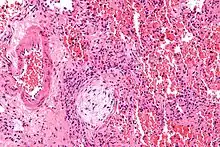

| Micrograph showing a Masson body (off center left/bottom of the image – pale circular and paucicellular), as may be seen in cryptogenic organizing pneumonia. The Masson body plugs the airway. The artery associated with the obliterated airway is also seen (far left of the image). H&E stain. | |

Organizing pneumonia is usually preceded by some type of lung injury that causes a localized denudation or disruption in continuity of the epithelial basal laminae of the type 1 alveolar pneumocytes that line the alveoli.[9] This injury to the epithelial basal lamina results in inflammatory cells and plasma proteins leaking into the alveolar space and forming fibrin, resulting in an initial fibroblast driven intra-alveolar fibroproliferation.[9] The fibroblasts differentiate into myofibroblasts and continue to form fibrosis resulting in intra-alveolar fibroinflammatory buds (Masson's Bodies) that are characteristic of organizing pneumonia.[9] These Masson's bodies consist of inflammatory cells contained in an extracellular matrix consisting of type I collagen, fibronectin, procollagen type III, tenascin C and proteoglycans.[9] Angiogenesis , or the formation of blood vessels, occurs in the Masson's bodies and this is driven by vascular endothelial growth factor.[9] Remodeling occurs, resulting in the intra-alveolar fibroinflammatory buds (Masson's Bodies) moving into the interstitial space and forming collagen globules that are then covered by type 1 alveolar epithelial cells with well developed basement membranes. These type 1 alveolar epithelial cells (pneumocytes) then proliferate, restoring the continuity and function of the alveolar unit.[9] This process is in contrast to the histopathologic changes seen in usual interstitial pneumonia where extensive fibrosis and inflammation occur leading to fibroblastic foci to form in the alveolar spaces resulting in obliteration of the alveolar space, scarring and significant damage to lung architecture (the alveoli).[9]

Biopsy findings in patients with organizing pneumonia consist of loose connective tissue plugs involving the alveoli, alveolar ducts and bronchioles. The loose connective tissue plugs occupying the alveolar spaces often connect to other connective tissue plugs in nearby alveoli via the pores of Kohn creating a characteristic butterfly pattern on histology.[9] There is usually minimal to no interstitial inflammatory changes in biopsies of organizing pneumonia.[9]

Histologically, cryptogenic organizing pneumonia is characterized by the presence of polypoid plugs of loose organizing connective tissue (Masson bodies) within alveolar ducts, alveoli, and bronchioles.